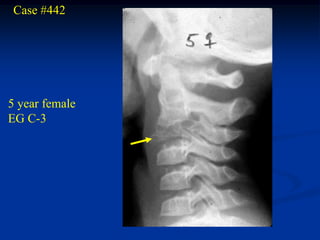

Case #442

5 year female

EG C-3